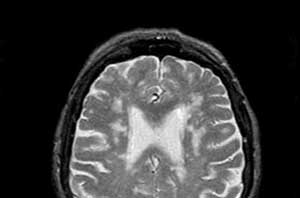

- магнитно-резонансная и компьютерная томография, которые помогут выявить патологические изменения в головном мозге;

Лейкоэнцефалопатия головного мозга представляет собой группу заболеваний, характеризующихся поражением белого вещества мозга. Врачи выделяют несколько видов, среди которых наиболее распространены лейкоэнцефалопатия, связанная с нарушением кровообращения, и метаболическая лейкоэнцефалопатия. Диагностика этих заболеваний включает в себя магнитно-резонансную томографию, которая позволяет визуализировать изменения в белом веществе, а также анализы на выявление возможных метаболических нарушений. Лечение зависит от причины заболевания и может включать медикаментозную терапию, направленную на улучшение мозгового кровообращения, а также реабилитационные мероприятия. Врачи подчеркивают важность ранней диагностики и комплексного подхода к лечению для достижения наилучших результатов.

Лейкоэнцефалопатия головного мозга — это заболевание, поражающее белое вещество мозга, что может приводить к различным неврологическим нарушениям. Люди часто обсуждают его виды, среди которых выделяют врожденную и приобретенную формы. Врожденная лейкоэнцефалопатия, как правило, связана с генетическими мутациями, тогда как приобретенная может возникать из-за инфекций, токсических воздействий или сосудистых заболеваний. Диагностика включает в себя МРТ, которое позволяет визуализировать изменения в белом веществе, а также анализы крови и другие исследования. Лечение зависит от причины заболевания и может включать медикаментозную терапию, реабилитацию и поддерживающую помощь. Многие пациенты и их семьи сталкиваются с трудностями в понимании болезни, что подчеркивает важность информирования и поддержки со стороны медицинских специалистов.